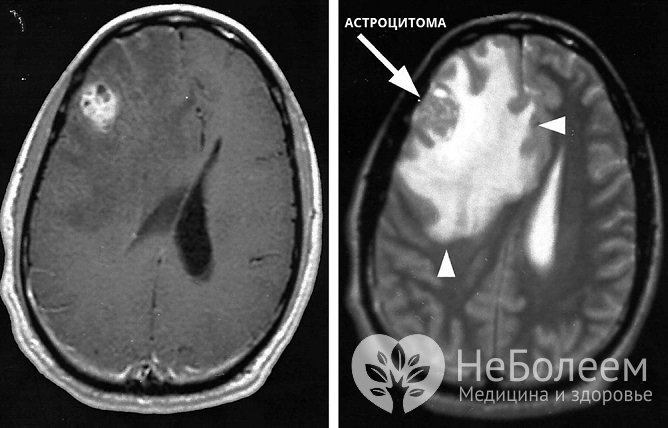

Для диагностики астроцитомы и ее особенностей проводится ангиографияПервичное инструментальное обследование при подозрении на астроцитому головного мозга состоит в проведении электроэнцефалографии (ЭЭГ) и эхоэнцефалографии (ЭхоЭГ). Выявленные изменения являются показанием для направления на магнитно-резонансную или компьютерную томографию головного мозга.

Точный диагноз с определением степени злокачественности опухоли можно поставить только по результатам гистологического анализа. Получить биологический материал для проведения этого исследования возможно при стереотаксической биопсии или в ходе оперативного вмешательства.